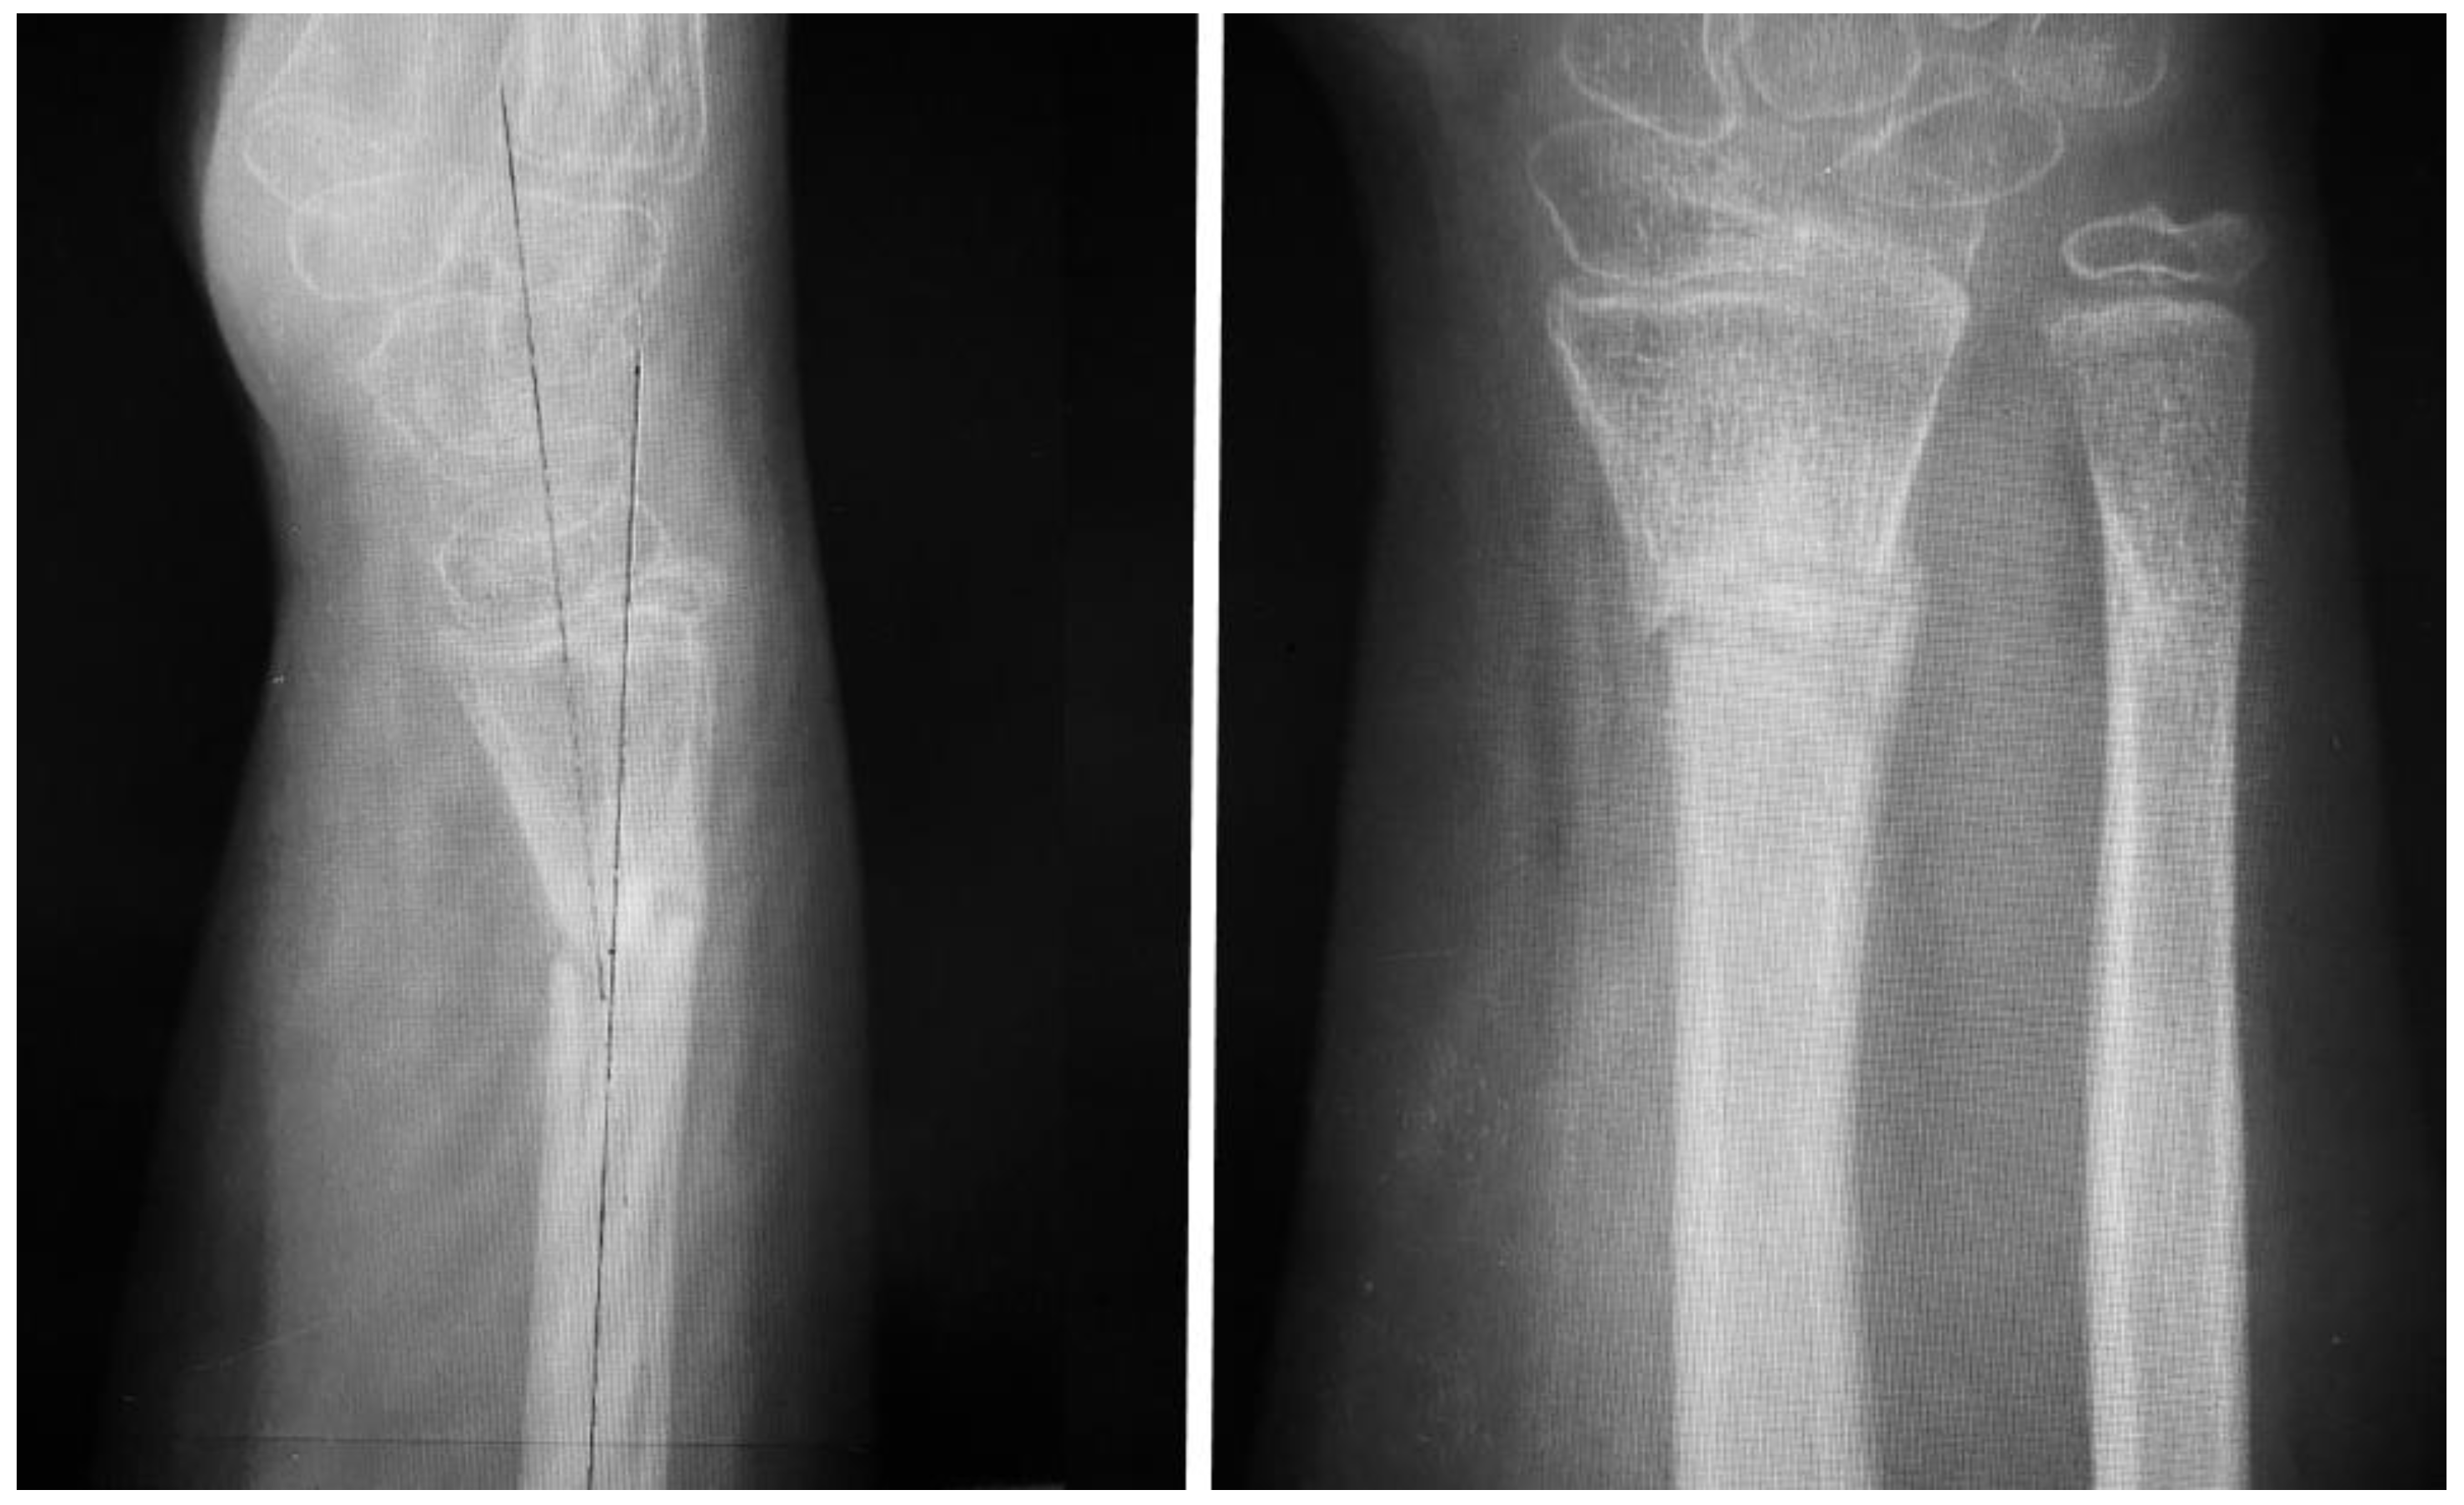

Follow-up exams were scheduled monthly, but the patient did not present until 6 months post-operatively, with pain over the forearm, increased pain with movement of the radiocarpal joint and thumb, moderate loss of range of motion and objective deformity of the distal forearm with no history of recent trauma. A plain radiograph was obtained (Figure 4).

Post-operatively, no immobilization was required and mobility was allowed as tolerated without loading the hand for four weeks. At this time, the passive range of motion was normal while the active range of motion was slightly limited for flexion and extension of the wrist, and the patient underwent a 4-week rehabilitation program involving physical therapy exercises and mobility exercises. At 6 weeks post-operation our patient was pain-free with full range of motion. At week 8 the patient started strengthening exercises, and was allowed to return to high-demand sports after the 4-month follow-up clinical evaluation, which revealed full range of motion, passive and active, and no pain when loading the hand during active flexion and extension. At 12 months, we obtained a radiological control image (Figure 6) that confirmed healing and adequate callus formation as well as bone remodeling.

Figure 4. AP and lateral views obtained at 6 months after rehabilitation failure and recurrent pain with movement, demonstrating a lack of union and gross angulation of the radius and good healing of the ulna.

Figure 6. The 12-month follow-up plain radiographs demonstrating good healing and proper callus formation.